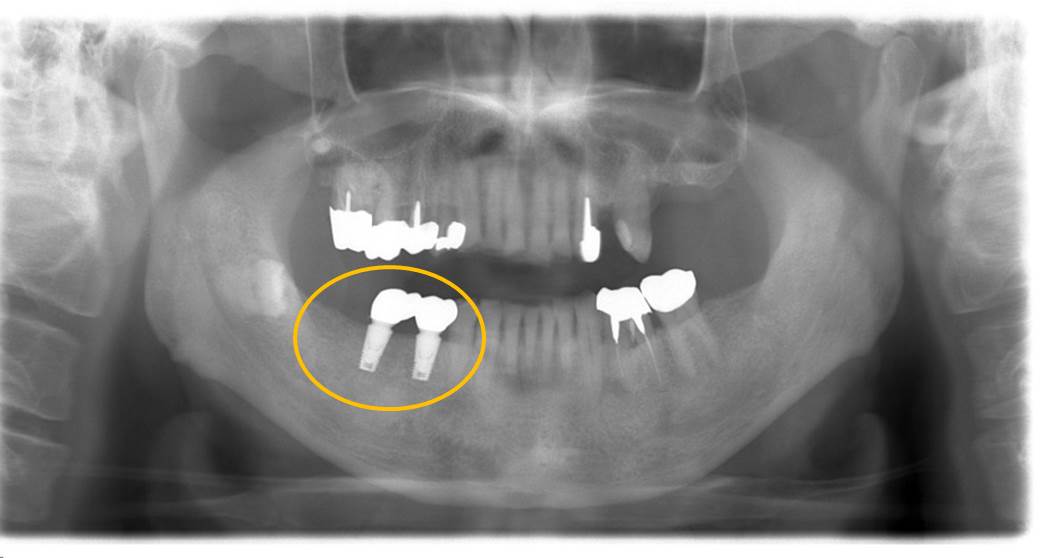

術後のエックス線写真です。

問題なくインプラントが埋入されています。

歯周病の問題もなく、4か月ごとのメインテナンスを行っています。